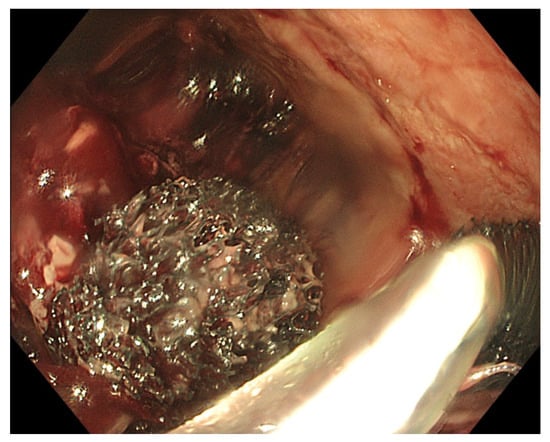

5.2. Intra-Procedure Difficulties

5.3. Post-Procedure Difficulties